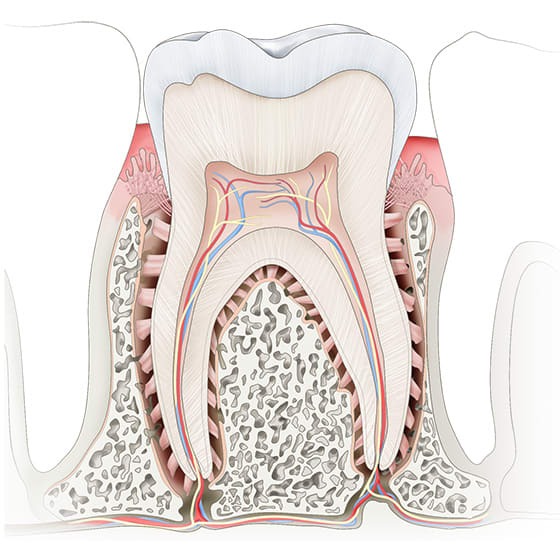

ریشه دندان

مهم ترین قسمت دندان و اصلی ترین قسمت دندان ریشه دندان می باشد که دارای بافت و عصب ها می باشد ریشه دندان در درون استخوان قرار دارد و باعث فیکس شدن دندان در جای خود می شود تقریبا دو سوم کل دندان را تشکیل می دهد .

ریشه دندان از چندین بخش تشکیل شده است که عبارتند از :

کانال ریشه

سمنتوم یا سمان به این ماده سمنت یا سیمان دندان نیز اطلاق می شود .

رباط پریودنتال از بافت همبند و فیبر کلاژن ساخته شده است .

اعصاب و رگ های خونی

استخوان فک

لثه ها

پالپ

حفره پالپ

تاج دندان

مینای دندان

عاج دندان

دندان ها از چه چیزی ساخته شده اند ؟

1 تاج و ریشه و گردن

2 مینا

3 لثه

4 عاج

5 اتاقک پالپ

6 کانال ریشه

7 رباط پریودنتال

8 کانال های فرعی

9 سوراخ آپیکال

10 استخوان آلوئول